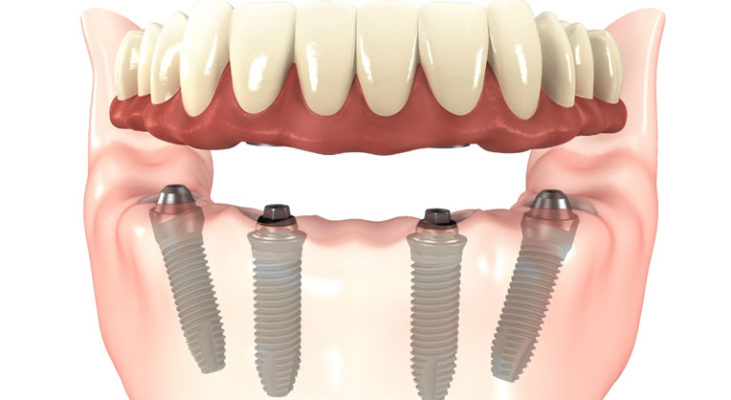

3. All-on-4 and  All-on-6

A full fixed bridges anchored to dental implants is an ideal and permanent solution for edentulous jaw. It is stable and provides high esthetics. It feels similar to having a new set of teeth again. Full implant bridges is however relatively costly and will need good bone condition for placement in each area.

Implant supported dentures provides for a more economical full jaw replacement solution. Implants allow you to wear full dentures (overdentures) without worrying that they will slip or fall out. The implants posts support and retain the dentures in place. This also means that the base of the denture can be made much smaller and made more comfortable. For overdentures, implants with screws placed in the jaw. They serve as attachments for a metal bar, a ball or a locator which snaps and locks the removable denture.

All-on-4/ All-on-6 and zygoma implants are immediate function and graftless solution implants. The implant concept tilts posterior implants to maximum jaw bone volume on the anterior area. Where there is insufficient bone, long zygomatic implants may be placed to hold a fixed hybrid denture in place.